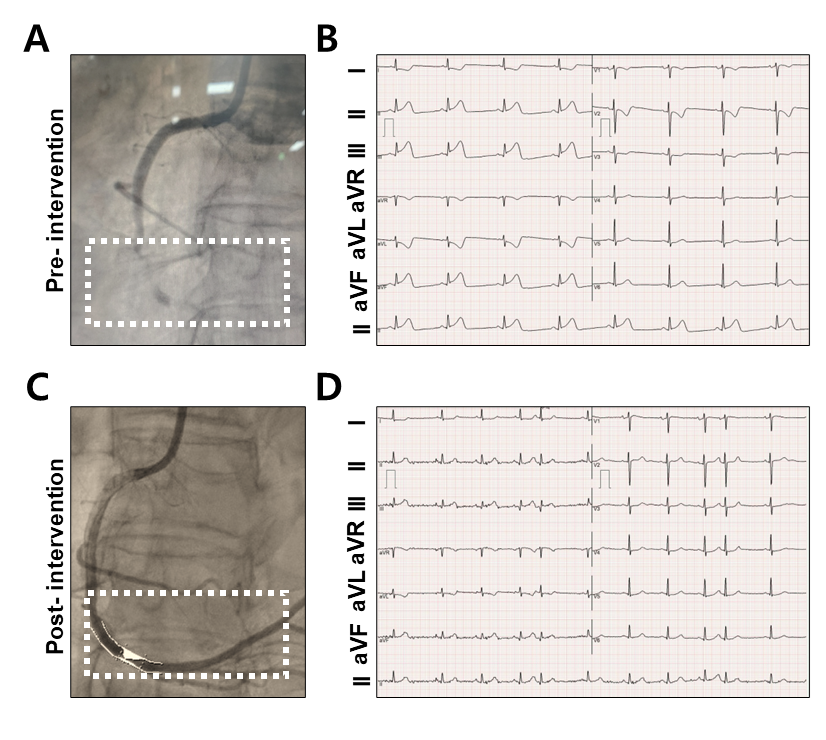

Figure 1. (A) Baseline coronary angiography showing total occlusion at the distal right coronary artery (white arrow), consistent with the culprit lesion in inferior STEMI. No distal flow is visualized beyond the occlusion. (B) Coronary tree schematic illustrating the location of the culprit lesion at the distal right coronary artery (dRCA), where a 3.5 × 33 mm drug-eluting stent (Xience sp) was deployed. The stented segment is shaded in blue, corresponding to the site of total occlusion treated during primary PCI.

Figure 2. Sequential coronary angiographic images demonstrating the stages of stent deployment in the distal right coronary artery (dRCA). (A) SION blue-intervention image. (B) IVUS image. (C) Stent deployment using a 3.5 × 33 mm drug-eluting stent (white arrow). (D) Balloon inflation during post-dilatation (white arrow). (E) Final angiogram confirming restored 1 flow and well-expanded stent (white arrow).

Figure 3. Coronary angiography and Electrocardiogram (ECG) findings before and after intervention. (A) Pre-intervention coronary angiography shows total occlusion of the distal right coronary artery (RCA) within the dotted box. (B) Corresponding 12-lead ECG reveals ST-segment elevation in leads II, III, and aVF, consistent with acute inferior myocardial infarction. (C) Post-intervention angiography after primary percutaneous coronary intervention demonstrates successful reperfusion of the distal RCA with restored TIMI grade 3 flow (dotted box). (D) Follow-up ECG shows resolution of ST-segment elevations in the inferior leads and normalization of QRS morphology, indicating successful myocardial reperfusion